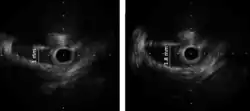

Various imaging tests have a potential to identify coronary artery anomalies. Echocardiography (ultrasound scanning of the heart) is simple, non-invasive and economical. Its use for CAAs screening is limited because its diagnostic sensitivity is highly dependent on the operator's skills and is significantly lower in larger individuals (>40 kg). The diagnostic power of echocardiography is generally poor in most cases after infancy. Especially if clinical suspicion for CAAs is high (e.g. syncope following exertion and/or history of aborted sudden cardiac death). Cardiac magnetic resonance (CMR) is an excellent tool to identify coronary artery anomalies with a significantly higher diagnostic accuracy than standard echocardiography. Compared to CMR, coronary computed tomographic angiography (CCTA) provides more precise assessment of coronary anatomy, course and degree of stenosis, but its clinical use for screening is strongly limited by its cost, the need for ionizing radiation, intravenous contrast and, in many cases, drugs administration. Assessment of severity of stenosis is best achieved by intravascular ultrasound (IVUS) imaging and it should be considered in known carriers of ACAOS-IM or that have symptoms or positive stress test results or are involved in competitive exercises. IVUS consists of cross-sectional imaging of coronary arteries in a catheterization laboratory by advancing a thin probe inside the vascular lumen, obtaining precise in-vivo information about degree of area stenosis in different arterial segments, providing a solid basis for treatment strategies.